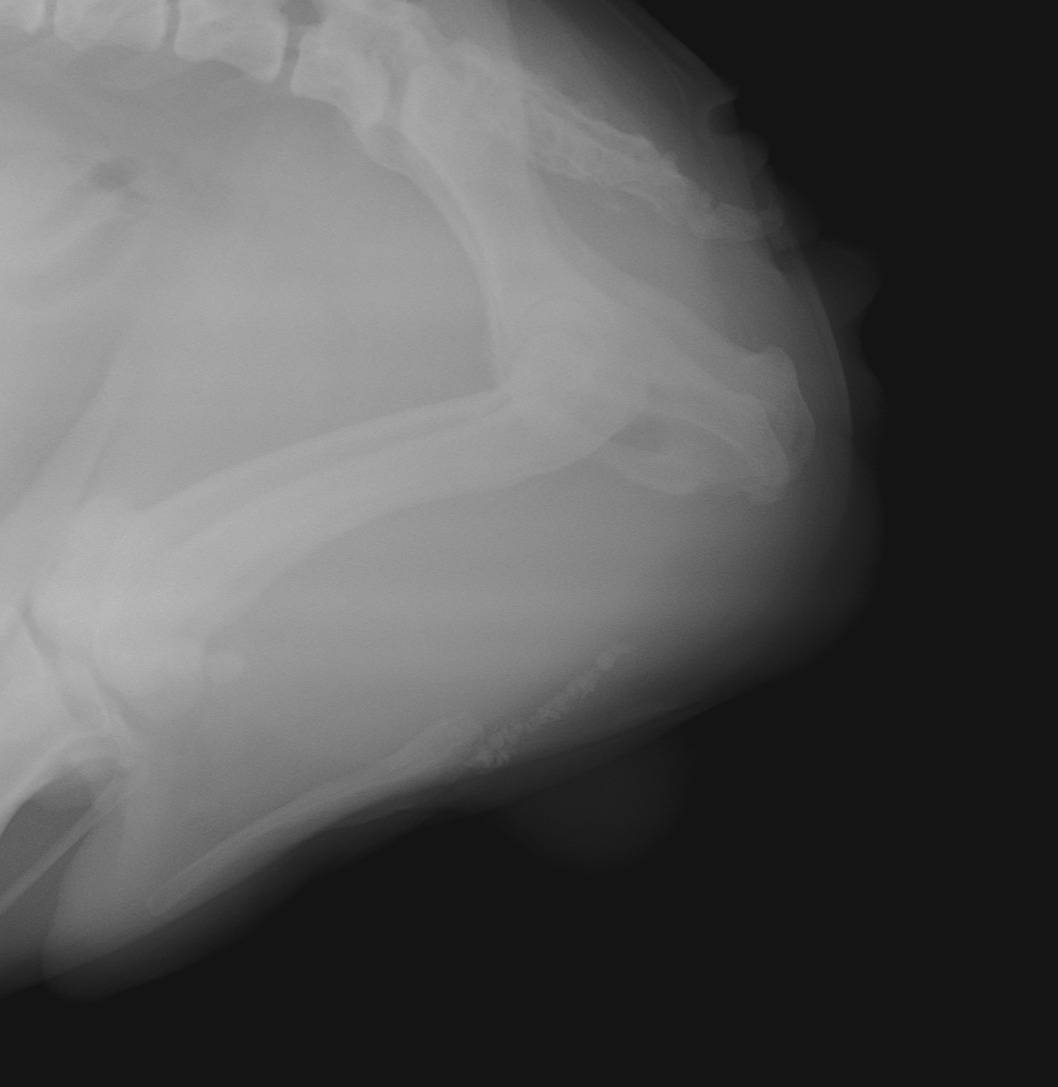

Nous pouvons alors pratiquer une uretrostomie, chirurgie qui consiste a créer un nouvel orifice en abouchant l’urètre directement a la peau dans sa zone la plus large et en amont du point d'obstruction.